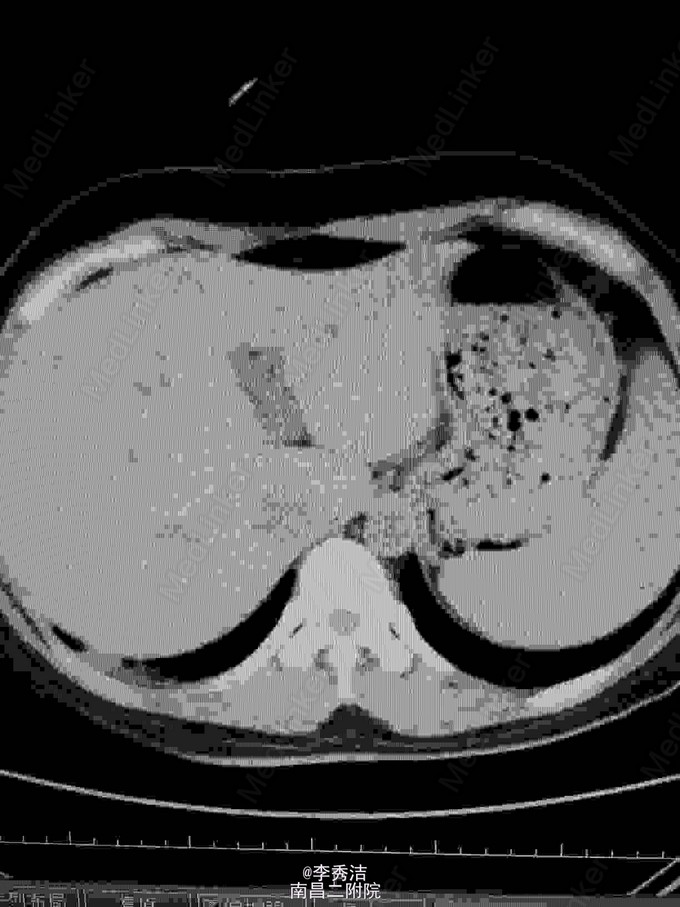

患者女,24岁,因“产后阴道不规则出血4月,发现妊娠滋养细胞肿瘤5天”入院。 患者于2014年12月11日足月自阴道分娩一胎儿(死胎)。后因阴道流血不尽,于2015年2月4日至当地医院清宫,未送病检。于2015年3月7日阴道血未干净至外地医院行第二次清宫,送病理报告示:(宫腔内刮出物)血块中见显著增生滋养叶细胞,核异形明显,考虑滋养叶细胞肿瘤,另见少量蜕膜组织。自诉6天前因阴道出血量多,明显多于月经量,至当地医院行阴道壁修补术。现无阴道流血,稍感下腹部隐痛,无头痛、发热等不适。门诊拟“阴道流血原因待查:滋养叶细胞肿瘤?”收入院。患者自发病以来,精神食欲睡眠可,大小便正常,体重无明显变化,否认高血压、糖尿病等慢性病史;否认传染病史;无食物药物过敏史,无手术及外伤史。平素月经规律,4~6天/33天,末次月经2014年3月26日,量中活动,暗红,有痛经,无血块。已婚,妊娠2,足月顺产2(1为死胎),未避孕。 查体:生命体征平稳,心肺听诊未及异常,腹平软,无压痛及反跳痛。妇检:外阴:已婚已产式;阴道:畅软,内见少量暗红色血液,前壁见两针丝线缝合;宫颈:光滑;宫体:平后位,超鸭蛋大小,质中、活动、无压痛;双附件未及异常。 辅助检查:2015年3月19日外院病理报告示:(宫腔内刮出物)血块中见显著增生滋养叶细胞,核异形明显,考虑滋养叶细胞肿瘤,另见少量蜕膜组织。血HCG209675mIU/ml。胸部CT示:肺部转移病灶。我院彩超示:子宫内混合回声团块,考虑滋养细胞肿瘤。 诊断:绒毛膜癌III期 诊疗计划:考虑患者为高危,使用联合化学药物治疗,5-FU+国产放线菌素D(更生霉素 KSM)。使用方法:5-FU 26~28mg/(Kg. d)+KSM6ug/(Kg. d)。静脉注射8天,每周检测血HCG水平一次。间隔13天进行第二次化疗。停药指证:HCG连续三次阴性后,继续给予三个疗程化疗。